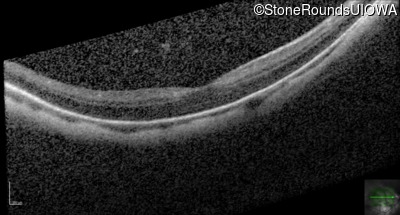

Age at visit: 20 years

OD OS